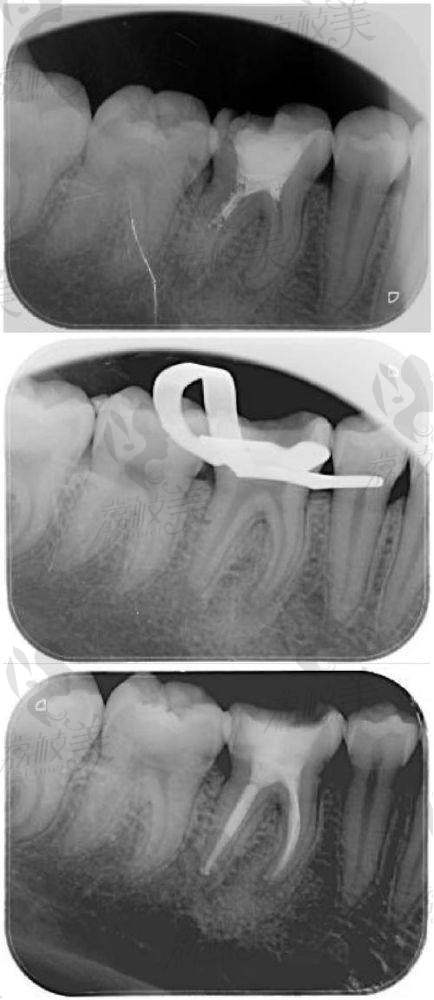

特别多初次接触这个手术名词的朋友,可能会困惑:根管治疗到底是干什么的?通俗地讲,它相当于“牙齿里的清根修复术”。我们的牙齿里面藏着一堆微细的“纳米毛细根管”,当龋齿感染深入牙髓后,细菌就会沿着这些根管扩散,造成剧痛甚至牙齿失活。

而根管治疗,就是清理这些受感染或坏死的牙髓组织,然后进行消毒、填充,再通过牙冠封闭,维持牙齿功能的保留性治疗。特别多人说它是“保牙利器”,绝非夸张!其实每年在国内完成的同类型治疗项目上百万例,已经成为牙医日常工作中使用更频繁的项目之一。

以下症状可做初步自查:牙齿剧痛无法缓解;冷热敏感持续时间超过30秒;牙齿变色、发黑或有瘘管形成小脓包;咀嚼时有明显酸胀;X片中可见明显牙根黑影等。如有这些表现,建议及时前往正规机构做全方面评估,以避免更大损伤。